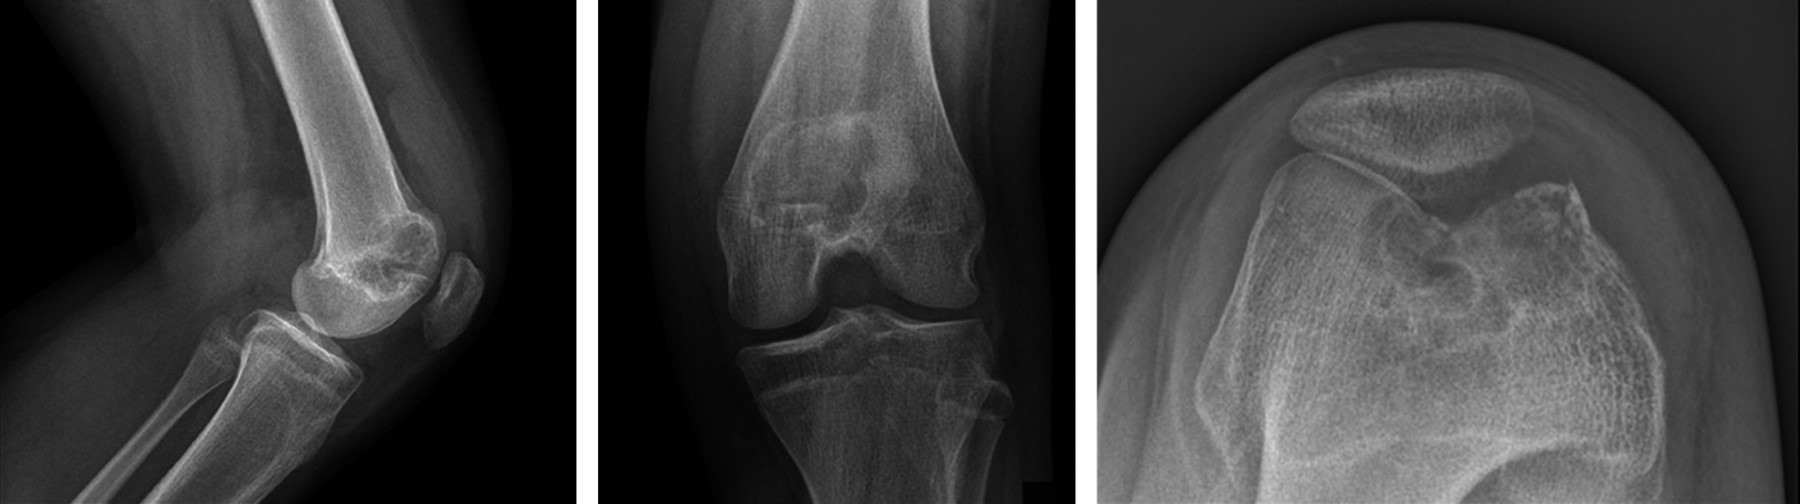

Se realizó el estudio complementario con TAC y RMN; en el cual la TAC de rodilla indicó una imagen lítica metafisaria de fémur distal de bordes circunscritos bien definidos con fractura en hueso patológico, sin colapso de la columna medial (Figura 2) y en la RMN en el corte T2 y supresión grasa, se observó una lesión de márgenes escleróticos sin signos de reacción perióstica, con relleno de aparente densidad líquida levemente heterogéneo, con aparente invasión fisaria, sin compromiso de partes blandas, siendo compatible con neoplasia de origen condral coincidiendo con la sospecha diagnóstica de condroblastoma de fémur distal (Figura 3).

Durante el seguimiento radiológico y clínico estricto, se realizó un control inicial al mes postoperatorio, seguido de controles cada tres meses (Figura 4). Durante el último mes previo al control de los siete meses postoperatorios, la paciente presentó dolor constante afebril y sensación de calor local, sin otros signos de infección. Debido a estos síntomas, se solicitó una RMN de control con contraste, ésta reveló una pequeña lesión endomedular en la metáfisis distal de fémur, sugestiva de un foco de recidiva (Figura 5). Ante este hallazgo, se decidió una nueva intervención en la cual se realizó un segundo curetaje con biopsia, confirmando el diagnóstico de recidiva de condroblastoma. En esta intervención, no se aplicó injerto adicional y se optó por una resección intralesional completa sin adyuvancia.

La paciente se mantuvo, posterior a la segunda intervención, sin nuevos síntomas, con controles radiológicos periódicos, sin nuevos hallazgos. Consultó a los tres años postoperada por dolor anterior de rodilla, sin antecedente de trauma, describiéndose una rodilla estable, sin aumento de volumen ni de temperatura local, con dolor ubicado en relación a la articulación patelofemoral. Se tomaron imágenes radiográficas y TAC de rodilla izquierda en las que se muestra la presencia de una lesión quística postoperatoria en región metafisaria, no sugerente de recidiva (Figuras 6 y 7). Este cuadro se manejó de manera efectiva con fisioterapia enfocada en fortalecimiento muscular y propiocepción.